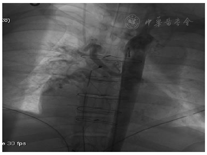

造影测压:肺动脉压47/15/26 mmHg,右室103/12 mmHg,三尖瓣上40/5 mmHg,右心房测34/27 mmHg(图5)。